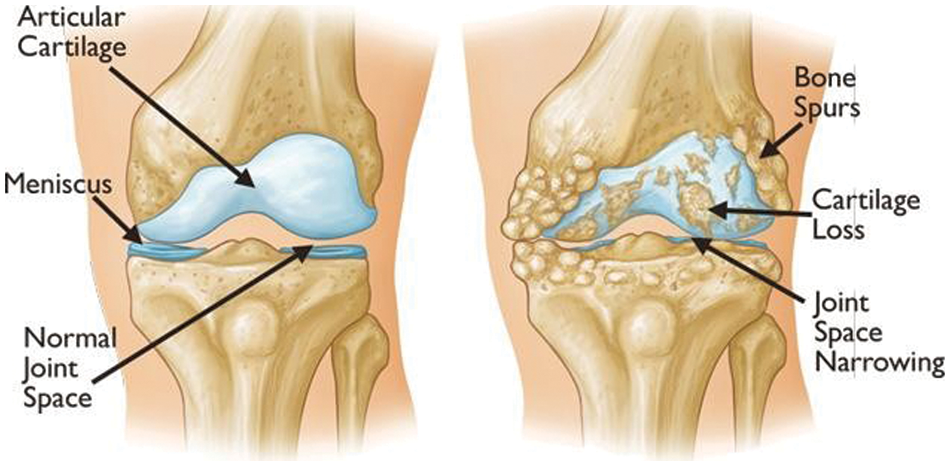

The human body is composed of numerous joints that allow it to move. Articular cartilage, which is the most vital tissue for maintaining normal joint function, is located between the joints to prevent the bones from colliding. The cartilage is indispensable for body movement and is one of the largest and most complex joints in the body. Cartilage is consistently used in everyday life, thus natural wear and tear during childhood, adolescence and old age can lead to symptoms based on a variety of causes; and physical-contact athletes, as well as age, are at increased risk of cartilage rupture. Activity and age are common causes, and degenerative arthritis (also known as osteoarthritis) may occur based on a combination of additional factors, including family history, obesity, diabetes, synovitis, systemic inflammatory mediators, innate immunity, lower body alignment, joint shape, and inflammation due to dysplasia, trauma and metabolic syndrome. It is the most common joint disease that can occur in anyone, and it is a major cause of disability worldwide, and the number of people suffering from the disease will continue to grow owing to aging populations and increased obesity. These causes can be divided into correctable and uncorrectable causes. Among the modifiable factors, the most common symptom is obesity, with 1 pound (0.45 kg) of weight applying 2 to 4 pounds (0.9 to 1.8 kg) to the knee, and excessive body weight increases joint loading causing detrimental and adverse effects on the weight-bearing joints. Uncorrectable causes include genetic variants and congenital factors, and the most common risk factor is age. In Korea, more than 80% of patients over the age of 55 or almost all patients over the age of 75 are diagnosed with osteoarthritis of the knee through radiographic examination, as shown in Fig. 1. The diagnosis is based on the visual changes shown in Fig. 2, such as localized articular cartilage and joint deformity, and is based on the patient's opinion of chronic pain, stiffness, and limited range of movement of the joint. If the cartilage suffers from severe wear and tear, it will cease to function normally, necessitating surgical or nonsurgical treatment. Nonsurgical treatment includes methods such as physical therapy, exercise therapy, and medication. Surgical treatments, such as knee osteotomy and artificial joint replacement, are performed in cases in which the pain is too severe to maintain the lifestyle, the pain does not improve even after six months of nonsurgical treatment, the structural deformation or instability of the joint is severe, or restrictions in range of motion are severe. However, there is a risk of infection during surgical treatment, which could necessitate re-surgery. Particularly in the case of artificial joint replacement treatment, as shown in Fig. 3, side effects, such as pain and functional failure, may be accompanied by structural instability after treatment. Owing to the limitations of surgical treatment, it is less burdensome to seek improvement through nonsurgical treatment with low side effects, and accurate diagnosis of arthritis is critical for early treatment to prevent surgical treatment. However, owing to the significant cost and time required to receive a diagnosis and a doctor’s opinion through the simple X-ray imaging process, most patients often go to the hospital only after a severe course and when everyday life is not possible. The scientific and logical evidence for the diagnosis and treatment of knee osteoarthritis is therefore increased, and evidence for standardized diagnostic and treatment methods that can be used in clinical settings must be performed [1–4].

Figure 2: Examples of visual symptoms that may appear during the onset of knee OA [1]

To apply deep learning to the actual medical world, it is necessary to show considerable accuracy, and scientific and logical evidence is required in the diagnosis process. Deep learning models for segmenting lesion areas or classifying lesion grades using X-ray images have been popularly adopted not only for degenerative arthritis problems but also for other problems, such as tuberculosis diagnosis [4]. Currently, research into medical artificial intelligence is actively being conducted. It is expected that through the various standardized diagnosis methods proposed in studies [5,6], doctors will be able to use more objective indicators to make faster and more accurate diagnoses. Therefore, if more accurate predictions can be made, deep learning can be used to prevent disease caused by degenerative arthritis. The existing procedure for diagnosing osteoarthritis is to first take radiographic images, as shown in Fig. 1, and then to consider the resulting images, which show the gradual reduction of joint spacing and deepening shadows of the bones under the cartilage. Furthermore, a questionnaire is administered to patients when determining the grade of osteoarthritis. Because this procedure allows for the diagnosis of osteoarthritis based on visual changes similar to those shown in Fig. 2, studies have been widely conducted to determine the grade of osteoarthritis using accumulated knee radiology images to train a deep learning model. Although deep learning models based on these visual changes enable information transfer to objective indicators, extensive research has been performed to improve the accuracy of osteoarthritis classification, which is necessary for practical use.